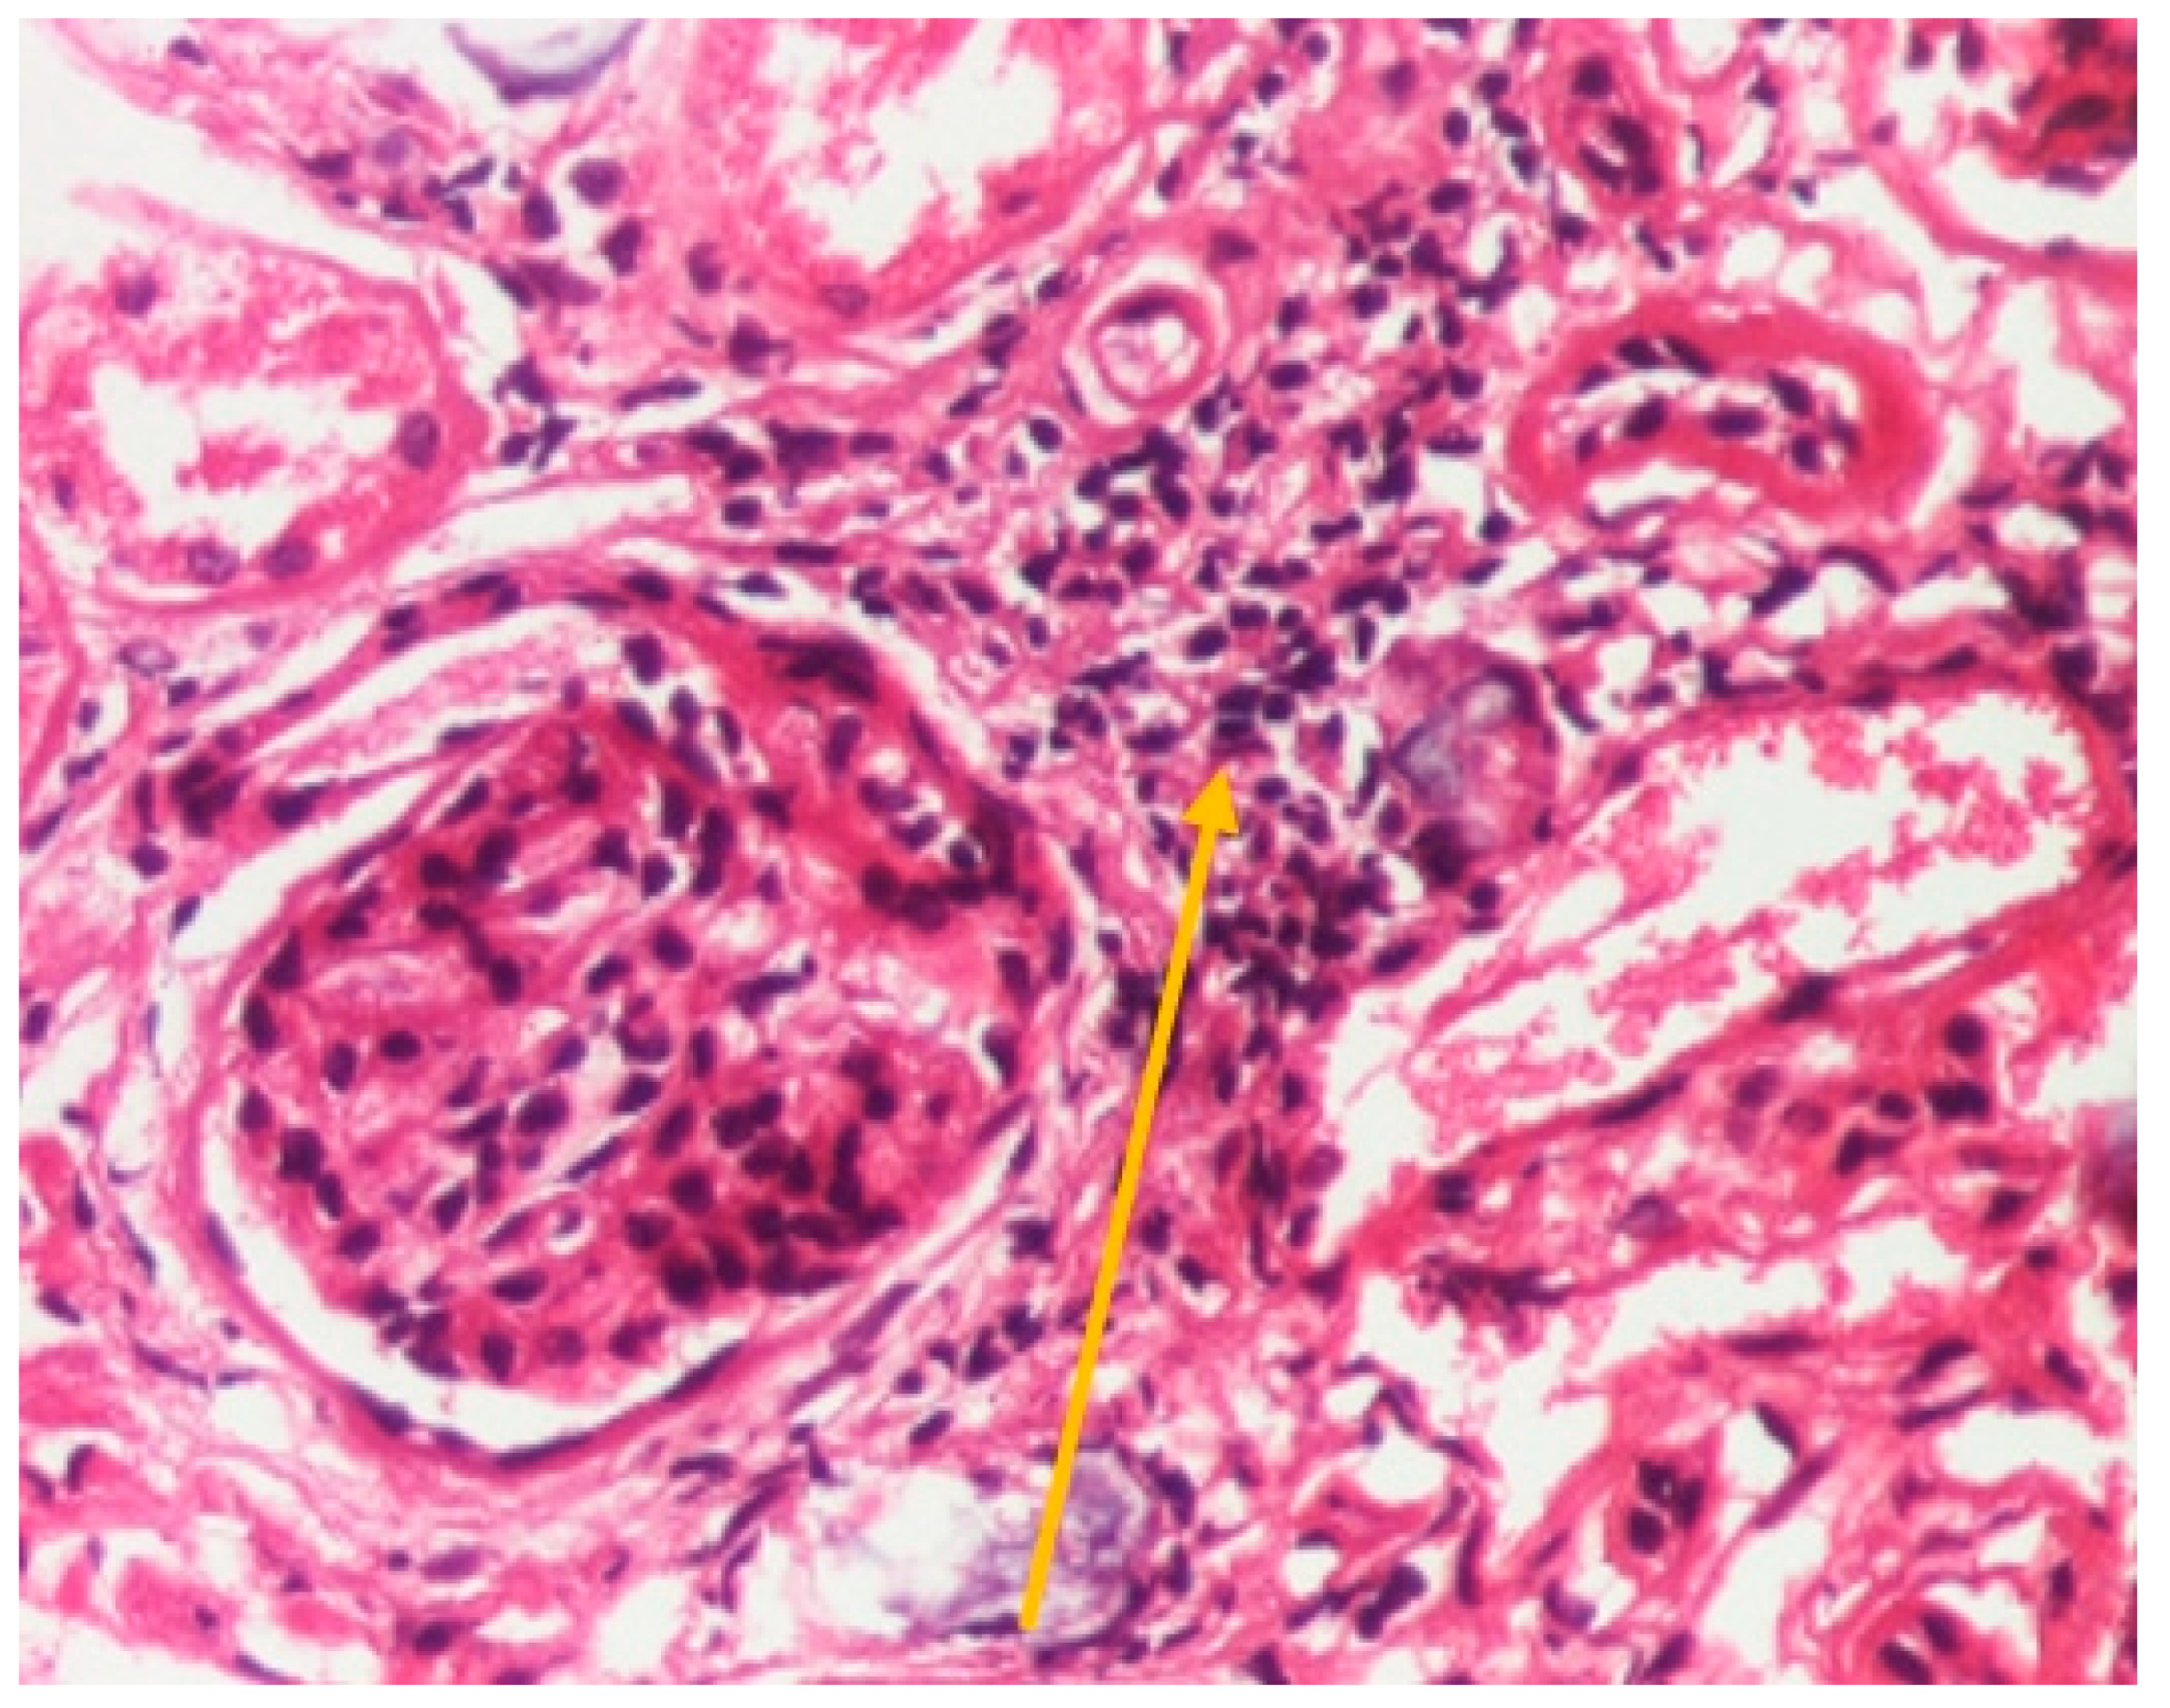

However, because of corticoid-related side effects (secondary Cushing syndrome), we decided to decrease the dose of prednisolone up to the maintenance dose of 0.25 mg/kg/day. Even though a clear histopathological diagnosis was made through hepatic punction, and renal involvement was almost certainly a consequence of sarcoidosis, this evolution prompted us to perform a renal biopsy. This showed non-granulomatous interstitial nephritis, nephrolithiasis, and interstitial fibrosis, as shown in Figure 7, Figure 8 and Figure 9. These images show no immune deposits in immunofluorescence, and no glomerulonephritis aspects, such as crescents or extent of mesangial proliferation.

Figure 7.

Hematoxylin-eosin staining ×200; renal tissue showing interstitial inflammation (yellow arrow) (personal collection, St. Mary Emergency Children’s Hospital, Iasi).